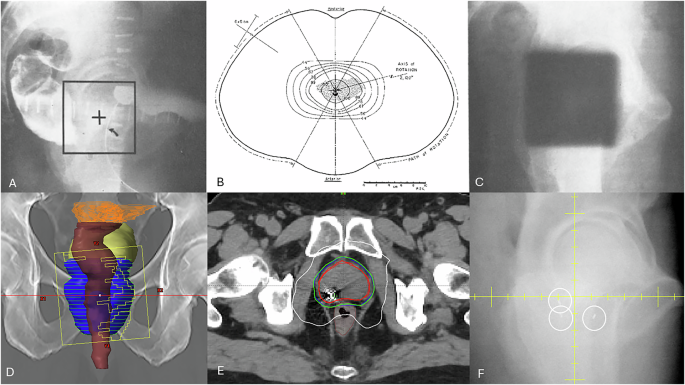

The authors further discuss a range of technological strategies proposed to mitigate the side effects associated with delivering treatment in fewer fractions. Approaches such as margin reduction enabled by fiducial markers or by MR-guided radiotherapy, intrafraction motion management, and adaptive treatment based on daily anatomy may contribute to reducing dose to adjacent organs at risk (OARs) and thereby lowering toxicity. Notably, several of these concepts—although now considerably more sophisticated—were already described over 60 years ago by Bagshaw et al. (Fig. 1A–F) [2] including early forms of anatomical surrogacy, volumetric targeting, and image guidance.

A Kilovoltage lateral simulator image used to set isocentre and field borders (square) based on inferential information of the prostate based on surrounding anatomy (rectal and bladder contrast, foley balloon, bony pelvis) B rotational therapy that creates an in-plane conformal delivery but lack of dynamic beams eye view shaping limits the ability to conform the beam to the actual prostate shape; such rotational delivery allowed the treatment of deep seated tumors with lower energy (1–4MV) x-rays C) image guidance using “port film” acquired by exposing an x-ray film prior to treatment showing alignment of the treatment beam (dark square) in relation to bony anatomy. D Digitally reconstructed radiograph of anterior view of pelvis reconstructed from CT imaging with superimposed contours for prostate (blue) rectum (brown) bladder (yellow) and MLC aperture design at start of a dynamic, intensity modulated arc (note the aperture is only treating part of the prostate) E conformal dose distribution from the volumetric dynamic arc therapy also demonstrating a fiducial marker used for image guidance F on board imaging used for dynamic tracking of the implanted fiducial marker during treatment.